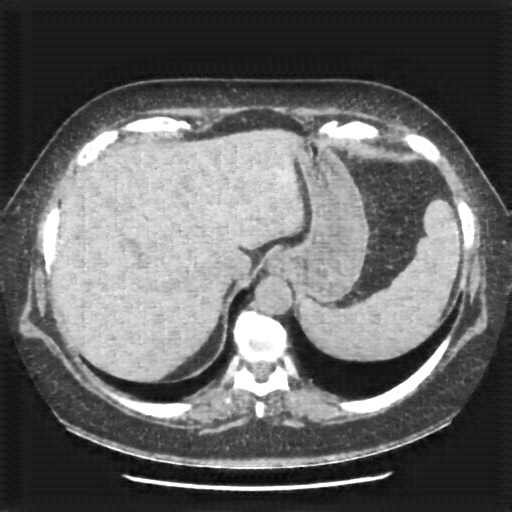

Original VENOUS CT scan

Full window (WL 1023.5, WW 4095 β†’ Low βˆ’1024, High +3071)

Actual HU range: [-160.0, 240.0]